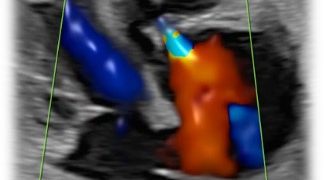

Guida al Counselling di Maggio 2025: patologie cistiche della fossa cranica posteriore

Cari colleghi, vi presentiamo la guida al counseling di Maggio 2025 sulla Patologia cistica della fossa cranica posteriore. Potrete scaricarla cliccando sul link. Grazie a Laura Sarno! ...